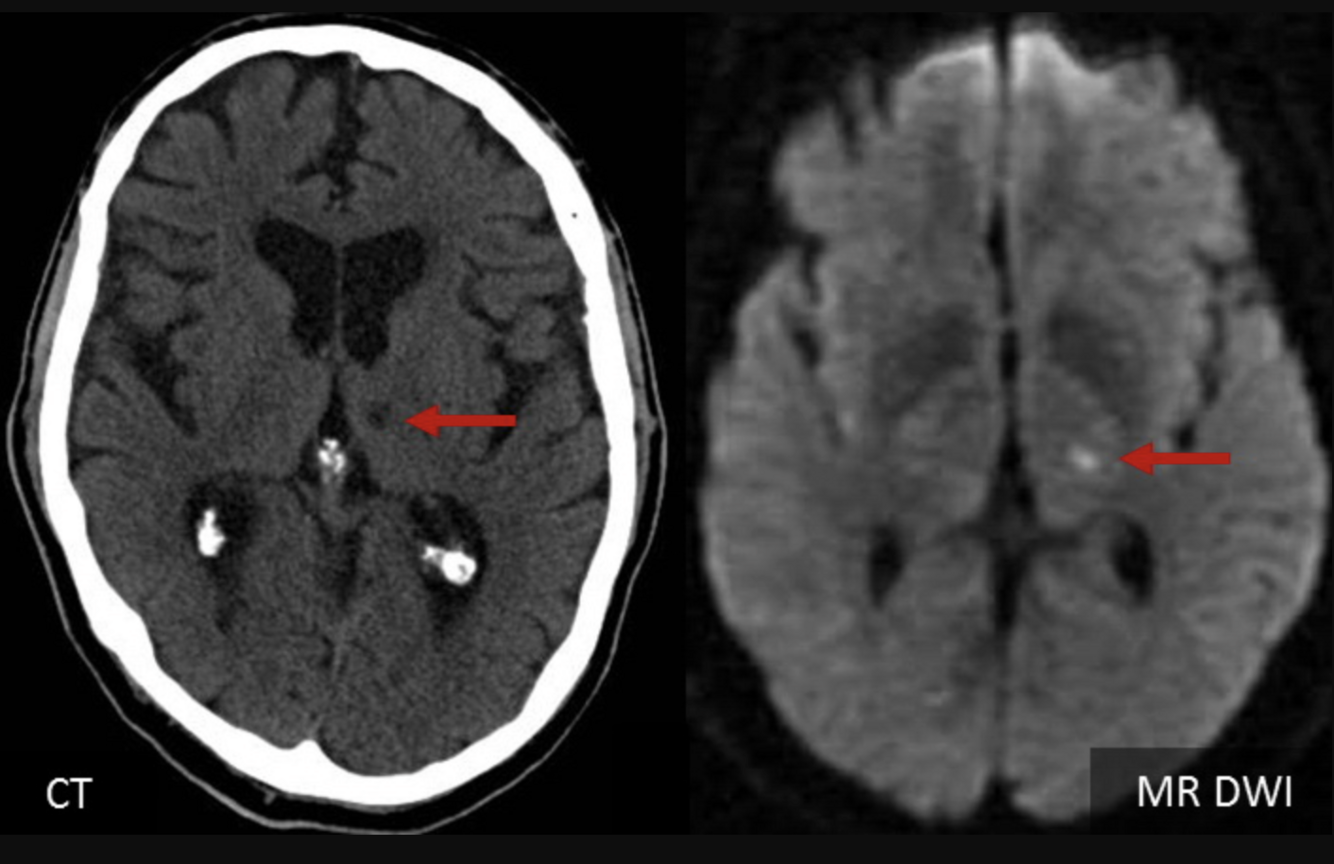

1. Up to 25% of noncontrasted head CT is unremarkable. Hence, obtain an emergent _diffusion-weighted MRI when this diagnosis is suspected